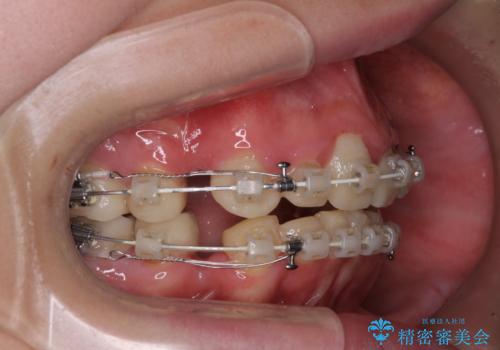

- 一時期の拒食症に伴い歯が酸で溶けてボロボロになってしまったとのことで来院された患者様です。

酸によりエナメル質の大半が溶けており、下顎前歯以外は酷いむし歯のような状態でした。

当初はほとんどの歯をむし歯治療のようにオールセラミッククラウンにて補綴治療を行う予定でしたが、仮歯に置き換えた時点で、口元の突出感や下顎前歯の叢生が気になるとのことで、上下左右の第一小臼歯4本を抜歯したワイヤー装置での抜歯矯正を行うこととしました。

矯正治療終了後に、残った歯をオールセラミッククラウンにて補綴治療を行うこととしました。